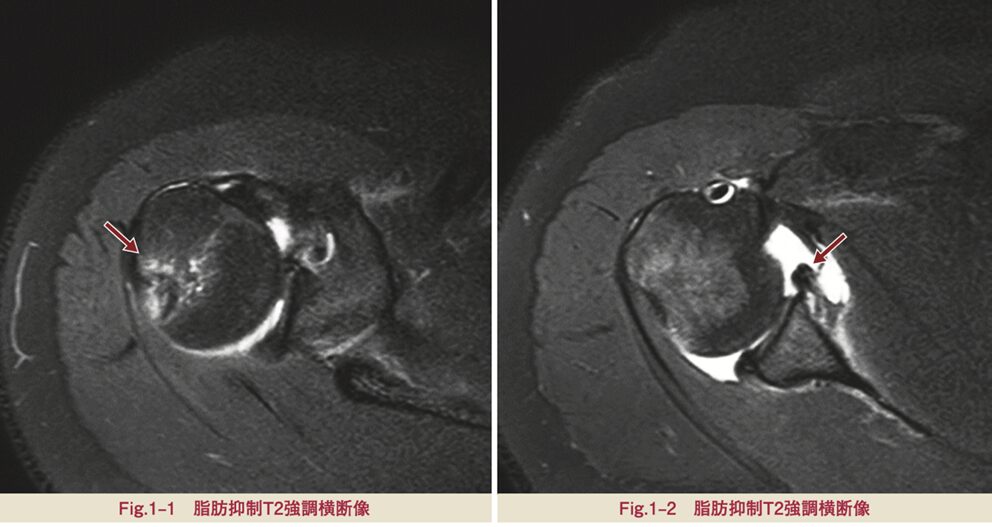

MRI検査

関節唇や関節包といった軟部組織の状態を詳しく評価するために極めて有用です。特に、造影剤を関節内に注入してから撮影するMRアースログラフィ検査は、バンカート損傷の範囲や程度を非常に鮮明に描き出すことができます。

出典: 天野大介. 2023. 「不安定肩」. 『臨床画像』39(1)